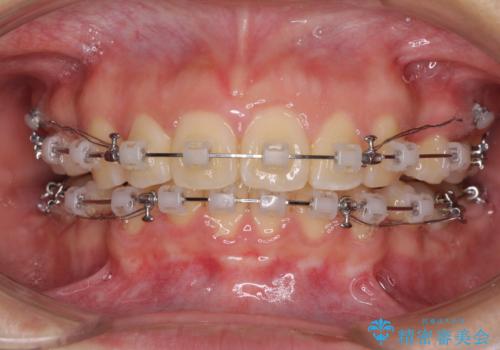

- 矯正装置

- クリアブラケット

- 上下前歯を部分矯正したところ出っ歯になってしまったとのことで来院された患者様です。

上下左右第一小臼歯4本を抜歯して、積極的に口元を引っ込めるよう、ワイヤー装置にて矯正治療を行うこととしました。